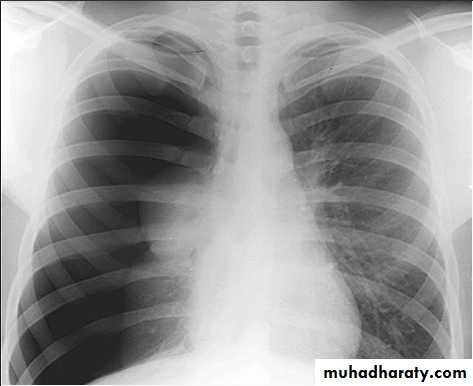

• Pleural effusion : collection of fluid within the pleural space. This can be further divided into Transudate , exudate, according to protein content .Other type of fluid collection within pleural space are

• Chest x-rays are the most commonly used examination to assess for presence of a pleural effusion, however it should be noted that on a routine erect frontal chest x-ray as much as 200-500 ml of fluid is

• required before it becomes evident .

blunting of the costophrenic angle

blunting of the cardiophrenic angle

fluid within the horizontal or oblique fissures

eventually a meniscus will be seen, on frontal films seen laterally and gently sloping medially

with large volume effusions, mediastinal shift occurs away from the effusion

• Lateral films are able to identify a smaller amount of fluid ( about75%)as the costophrenic angles are deepest posteriorly posteriorly

Pleura effusion signs

Obliteration of costo-pherinic anglesMeniscus sign

Lenticular sign